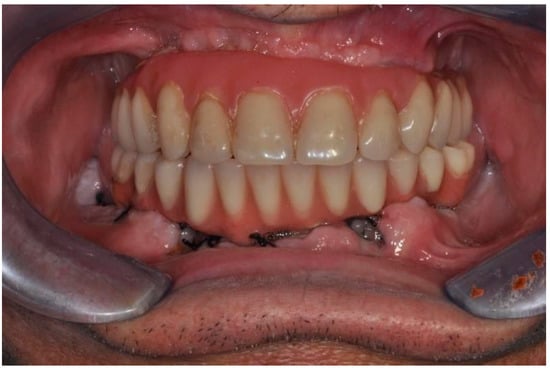

| Flanagan D. et al. [23] | J Oral Implantol | 2015 | clinical and radiographic: full-mouth radiographic series, panoramic and a bimaxillary cone beam computerized scan and mounted study casts | -One patient | Subject of 34 yo male; severely carious teeth and associated chronic abscesses (kidney transplant delayed) Comorbidities: IgA nephropathy, tabagism, hypertension and secondary hyperparathyroidism. Hemodialysis three times weekly. Ph. Therapy: Nephrocaps vitamin (B) supplement, amlodepine, besylate, cinacalcet, metoprolol, paroxetine. Bilateral compound ulnar and radial fractures, 2 blood transfusions. | Successfully treated with dental implant-supported fixed prostheses: fixed bimaxillary porcelain fused to metal implant-supported complete dentures |

| Hernández G. et al. [26] | Clin Oral Impl Res | 2019 | AI, MCI and TP reduction in mineral density of the cortical and trabecular bone in CRF patients and more severely in patients under haemodialysis compared to peritoneal dialysis | 1 IF in T | Mean follow-up of 116.8 months range from 84 to 192 months) | Renal transplant patients, are subjected pharmacological immunosuppression therapy |

| Flanagan D. et al. [23] | J Oral Implantol | 2015 | -Implant treatment for patients with IgA nephropathy (secondary hyperparathyroidism and osteodystrophy) may be successful. -Appropriate calcium therapy is important serum calcium to prevent inappropriate bone remodeling | 2 years | Long-term dialysis patient with end-stage renal disease (ESRD)also referred to as chronic kidney disease (CKD) due to IgA nephropathy complicated by severe secondary hyperparathyroidism and renal osteodystrophy | |